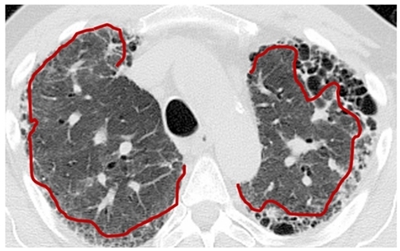

Médicos neumólogos especialistas se encargan de determinar el porcentaje del área total de los pulmones que se ve afectada por la fibrosis. Para esto, realizan una inspección visual de las imágenes de TAC, delimitan el área correspondiente a tejido fibroso, y determinan empíricamente el porcentaje de fibrosis pulmonar (%FP) en cada pulmón de acuerdo a su experiencia y conocimiento de la estructura del parénquima pulmonar sano, vías aéreas, vasculatura y patrón imagenológico de la enfermedad. Las características observadas por los médicos en la TAC son irregularidades intralobulares periféricas y quistes subpleurales con forma semejante a un panal de abejas (Figura 1), lo que significa que las regiones anormales del pulmón con huecos semejando un panal corresponden a regiones con fibrosis pulmonar [1,2].

Figura 1 Imagen de TAC de un paciente con presencia de fibrosis pulmonar donde el área afectada se visualiza de las líneas rojas hacía la parte externa. Los % de fibrosis pulmonar dados por el experto clínico son: 20% pulmón derecho, 40% pulmón izquierdo.